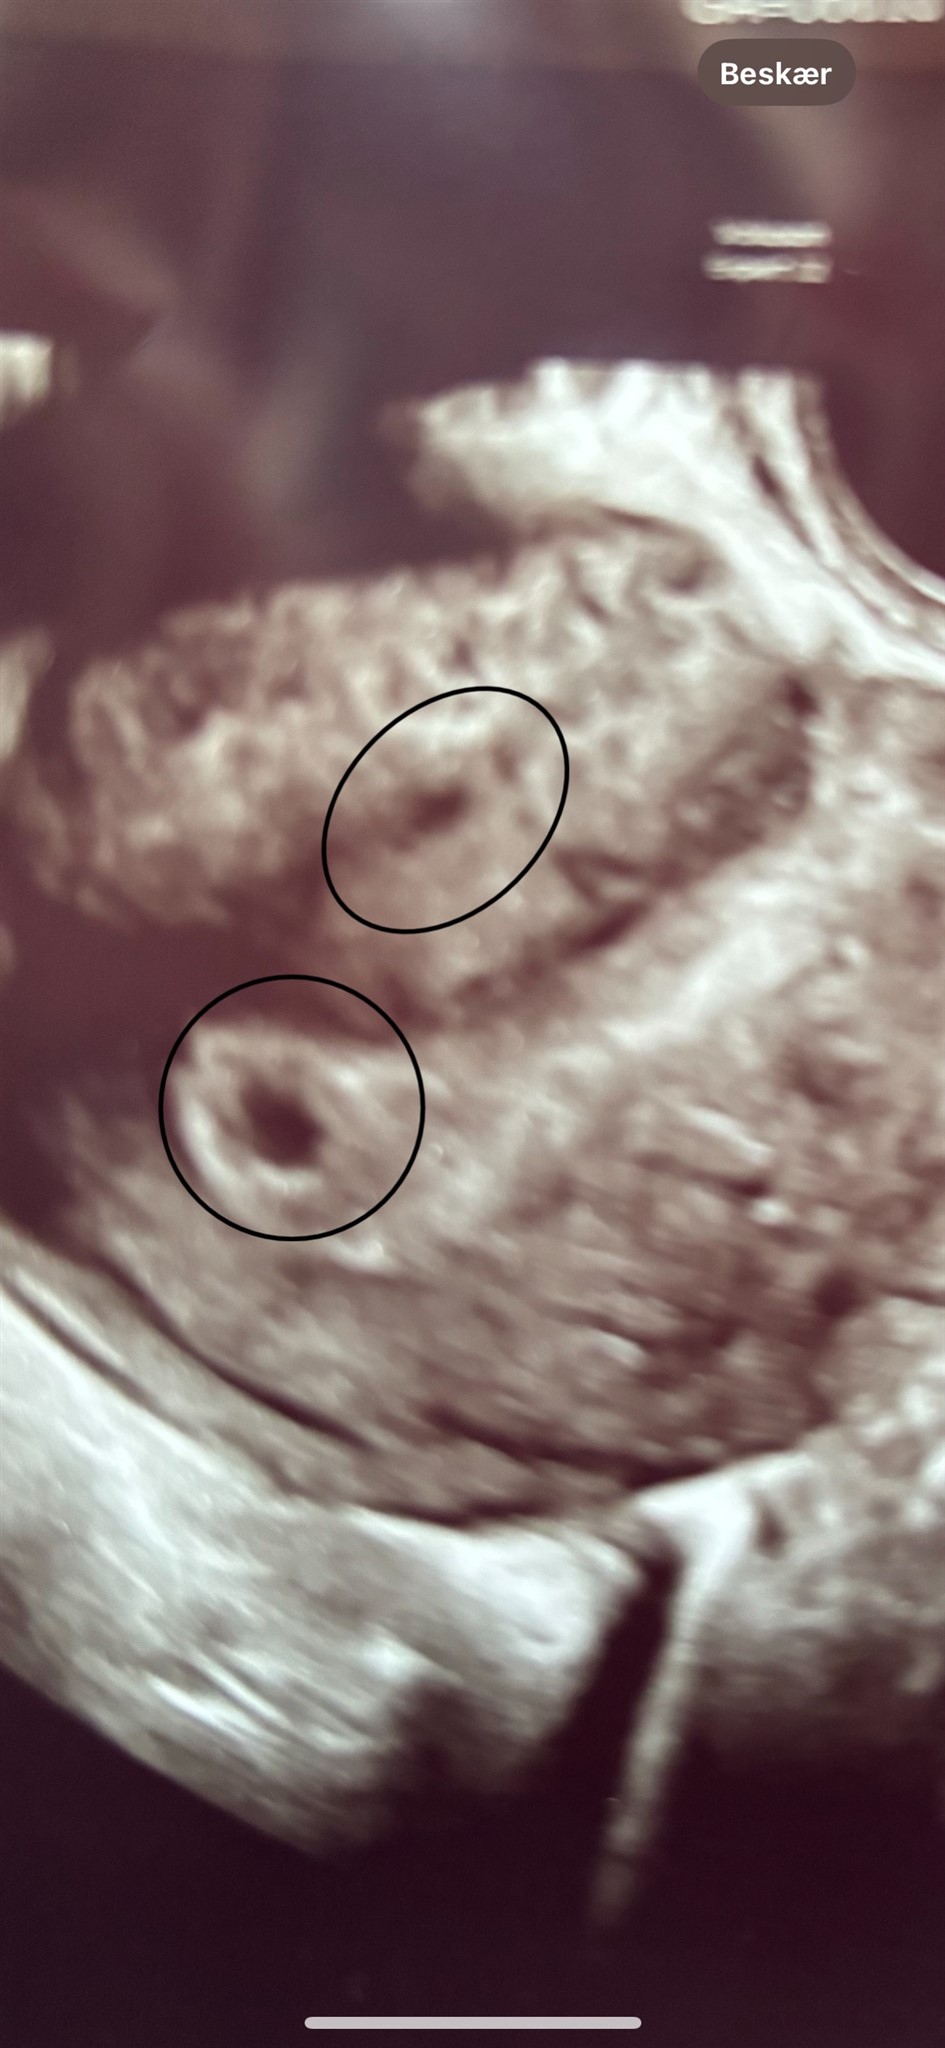

Synes også der kun er en på billedet? Hvor skulle nr 2 være ifht?

Vedhæftede fotos (klik for at se i fuld størrelse)

Det så jeg slet ikke… tror kun der er en, vil mit personlige gæt være.

Jeg synes kun det ligner en, den "anden" ligner ikke en graviditet synes jeg

Hvor tidligt er du blevet scannet? Jeg havde en lignende scanning med min søn omkring de 5 uger, og der var også en lille ekstra sort prik som ved dig. Gynækologen sagde, at det var meget normalt at se ved (så) tidlige scanninger, men at de sjældent udviklede sig til graviditeter. Så det ligner det samme for dig (og jeg var tydeligt kun gravid med én sæk 2 uger senere, hvor den anden prik var væk)